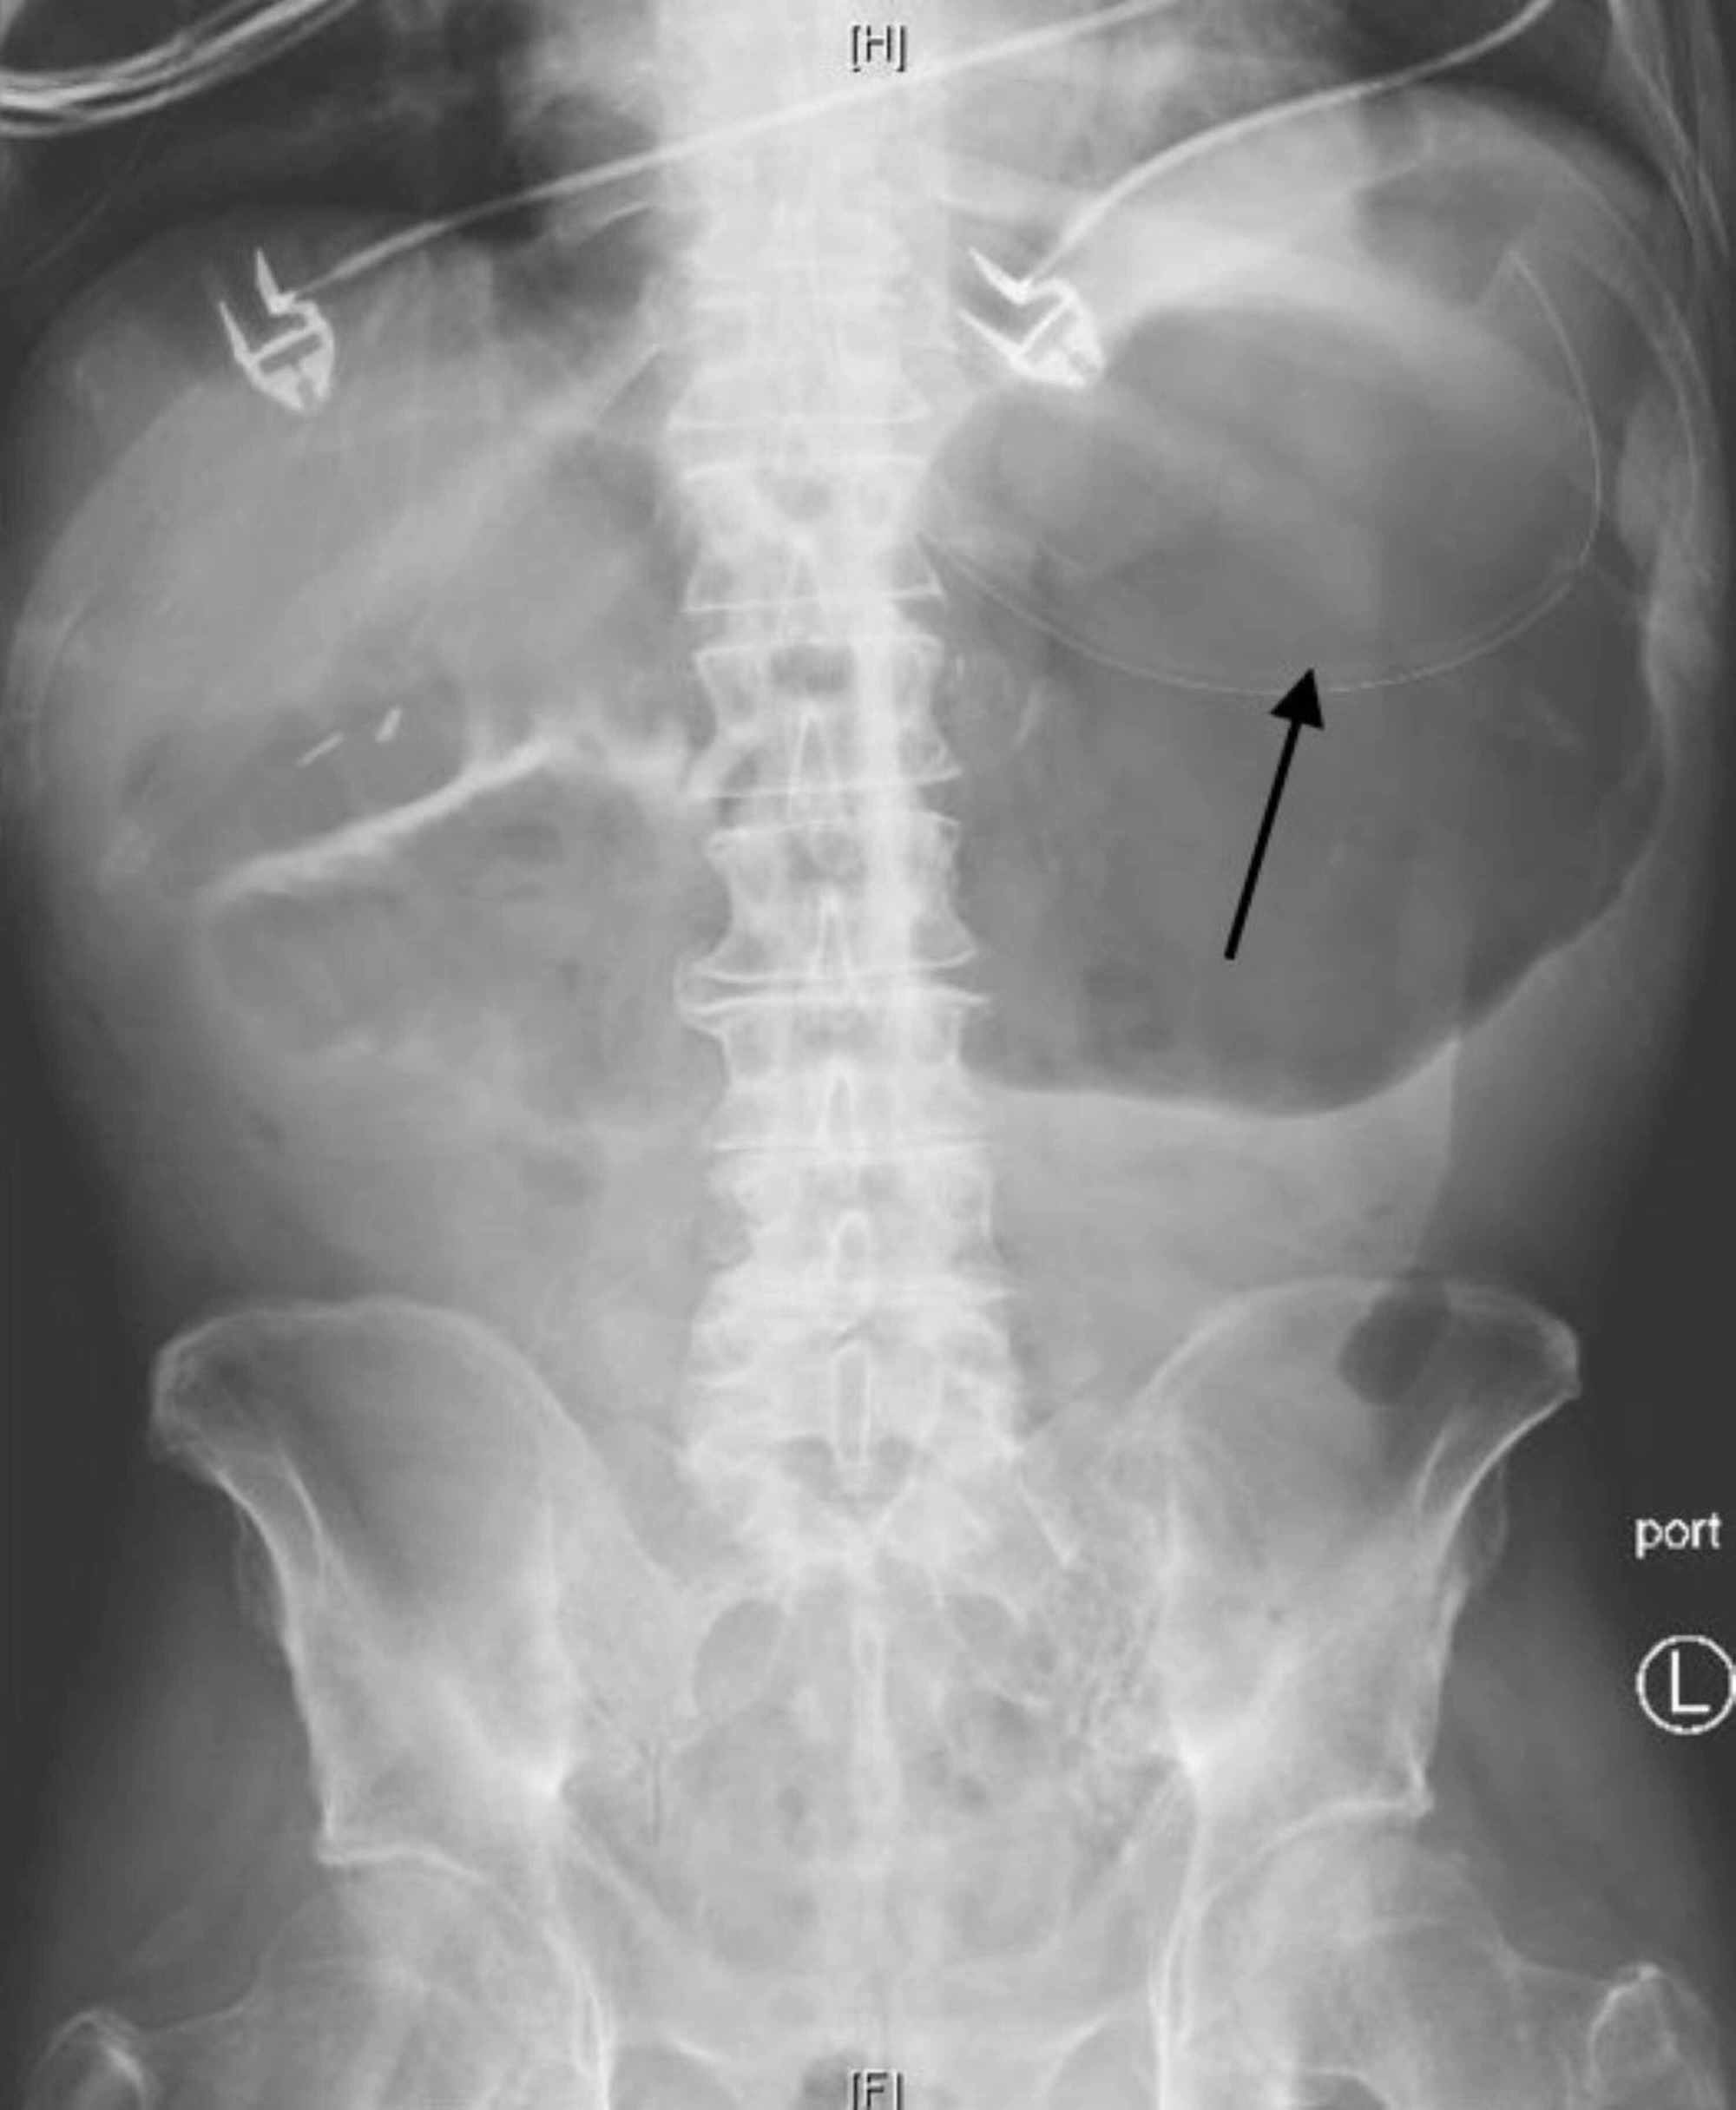

Crohn's disease with sacroiliac joint ankylosis Image

Plain abdominal radiographs in patients with Crohn’s disease Crohn's Disease Abdominal X Ray Upper gi series or barium swallow: Crohn’s disease (cd) is a systemic relapsing and remitting inflammatory bowel disease (ibd) that affects any segment of the. Crohn disease, also known as regional enteritis, is an idiopathic inflammatory bowel disease characterized by widespread. The lesions are usually transmural,. Indeterminate colitis is added to the list and represents ~6% of inflammatory bowel disease.. Crohn's Disease Abdominal X Ray.

Plain abdominal radiographs in patients with Crohn’s disease Crohn's Disease Abdominal X Ray Crohn disease, also known as regional enteritis, is an idiopathic inflammatory bowel disease characterized by widespread. Crohn’s disease (cd) is a systemic relapsing and remitting inflammatory bowel disease (ibd) that affects any segment of the. Indeterminate colitis is added to the list and represents ~6% of inflammatory bowel disease. Upper gi series or barium swallow: The lesions are usually transmural,.. Crohn's Disease Abdominal X Ray.

Plain abdominal radiographs in patients with Crohn’s disease Crohn's Disease Abdominal X Ray Crohn’s disease (cd) is a systemic relapsing and remitting inflammatory bowel disease (ibd) that affects any segment of the. Crohn's disease is characterized by inflammatory lesions in the gastrointestinal tract, most commonly in the terminal ileum and colon. You may receive an injection of. Crohn disease, also known as regional enteritis, is an idiopathic inflammatory bowel disease characterized by widespread.. Crohn's Disease Abdominal X Ray.

Abdominal distension in a patient with Crohn’s disease Gut Crohn's Disease Abdominal X Ray Crohn’s disease (cd) is a systemic relapsing and remitting inflammatory bowel disease (ibd) that affects any segment of the. Indeterminate colitis is added to the list and represents ~6% of inflammatory bowel disease. Crohn disease, also known as regional enteritis, is an idiopathic inflammatory bowel disease characterized by widespread. Upper gi series or barium swallow: You may receive an injection. Crohn's Disease Abdominal X Ray.

Abdominal distension in a patient with Crohn’s disease Gut Crohn's Disease Abdominal X Ray The lesions are usually transmural,. Upper gi series or barium swallow: Crohn disease, also known as regional enteritis, is an idiopathic inflammatory bowel disease characterized by widespread. You may receive an injection of. Crohn's disease is characterized by inflammatory lesions in the gastrointestinal tract, most commonly in the terminal ileum and colon. Crohn’s disease (cd) is a systemic relapsing and. Crohn's Disease Abdominal X Ray.